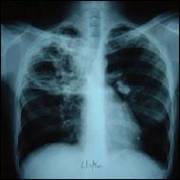

CANCERUL BRONHOPULMONAR

Este o tumoare maligna,cu punct de plecare bronsic.

SIMPTOME simptomele cancerului bronsic,atat cele de debut cat si cele tarzii,sunt in raport cu rectiile pe care le produce tumoarea la nivelul bronhieisi la nivelul parenchimului pulmonar.Unele infectii pot domina tabloul clinic si masca noplasmul.De aceea orice infectie pulmonara persistenta,recidivanta sau rebela la tratament,la un bolnav peste 40 anitrebuie sa sugereze si existenta unui cancer pulmonar.

TRATAMENTULchirurgical estesingurul eficace.Majoritatea bolnavilor ajung prea tirziu la interventia chirurgicala.Tratamentul medical este indicat in formele inoperabiledin cauza metastazelor,varstei inaintate,a complicatiilor.

Cancerul bronhopulmonar este cel mai des intalnit. Chiar si dupa ce au aparut acele mesaje pe pachetele de tigari, numarul bolnavilor nu scade in mod real. De fapt, americanii au ajun la un rezultat abia dupa 10 ani de campanie sustinuta .